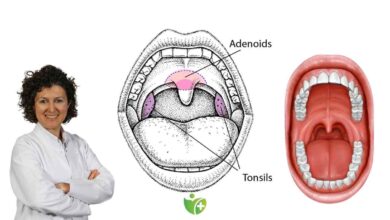

Gırtlak kanseri kesin tanısı nasıl konulur

Gırtlağında lezyon tespit edilen hastalar genel anestezi altında direkt laringoskopi denilen yöntemle ameliyat mikroskopu yardımıyla değerlendirilir. Laringoskop adı verilen enstürman hasta genel anestezi altındayken ağız yoluyla gırtlak a yerleştirilir ve ameliyat mikroskobunun büyütmesi ile ayrıntılı bir inceleme yapılıp lezyondan biyopsi yapılır.

Patolojik inceleme

Patolojik inceleme sonrasında kanser tanısı konulur. Bu kanserlerin çoğunluğu (%95) mukozadan köken alan skuamöz hücreli kanserdir. Kanser tanısı alan hasta uygun tedaviye alınır (bkz Gırtlak Kanseri Tedavisi). Patoloji inceleme sonucunda kanser öncesi evre olan “displazi” tanısı da konulabilir. Displazi hafif, orta veya şiddetli derecelerde olabilir. Displazi kanser olmamakla beraber, kanserin habercisidir. Bu nedenle dikkatle ele alınmalı ve uygun tedaviler yapılmalıdır.